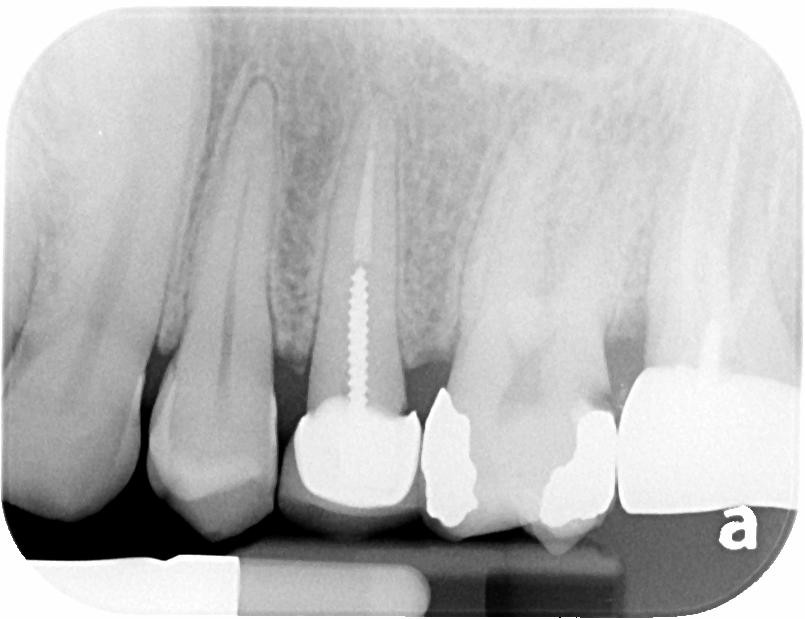

2. What option can describe the post placement in the X ray bellow for the tooth # 4.6?